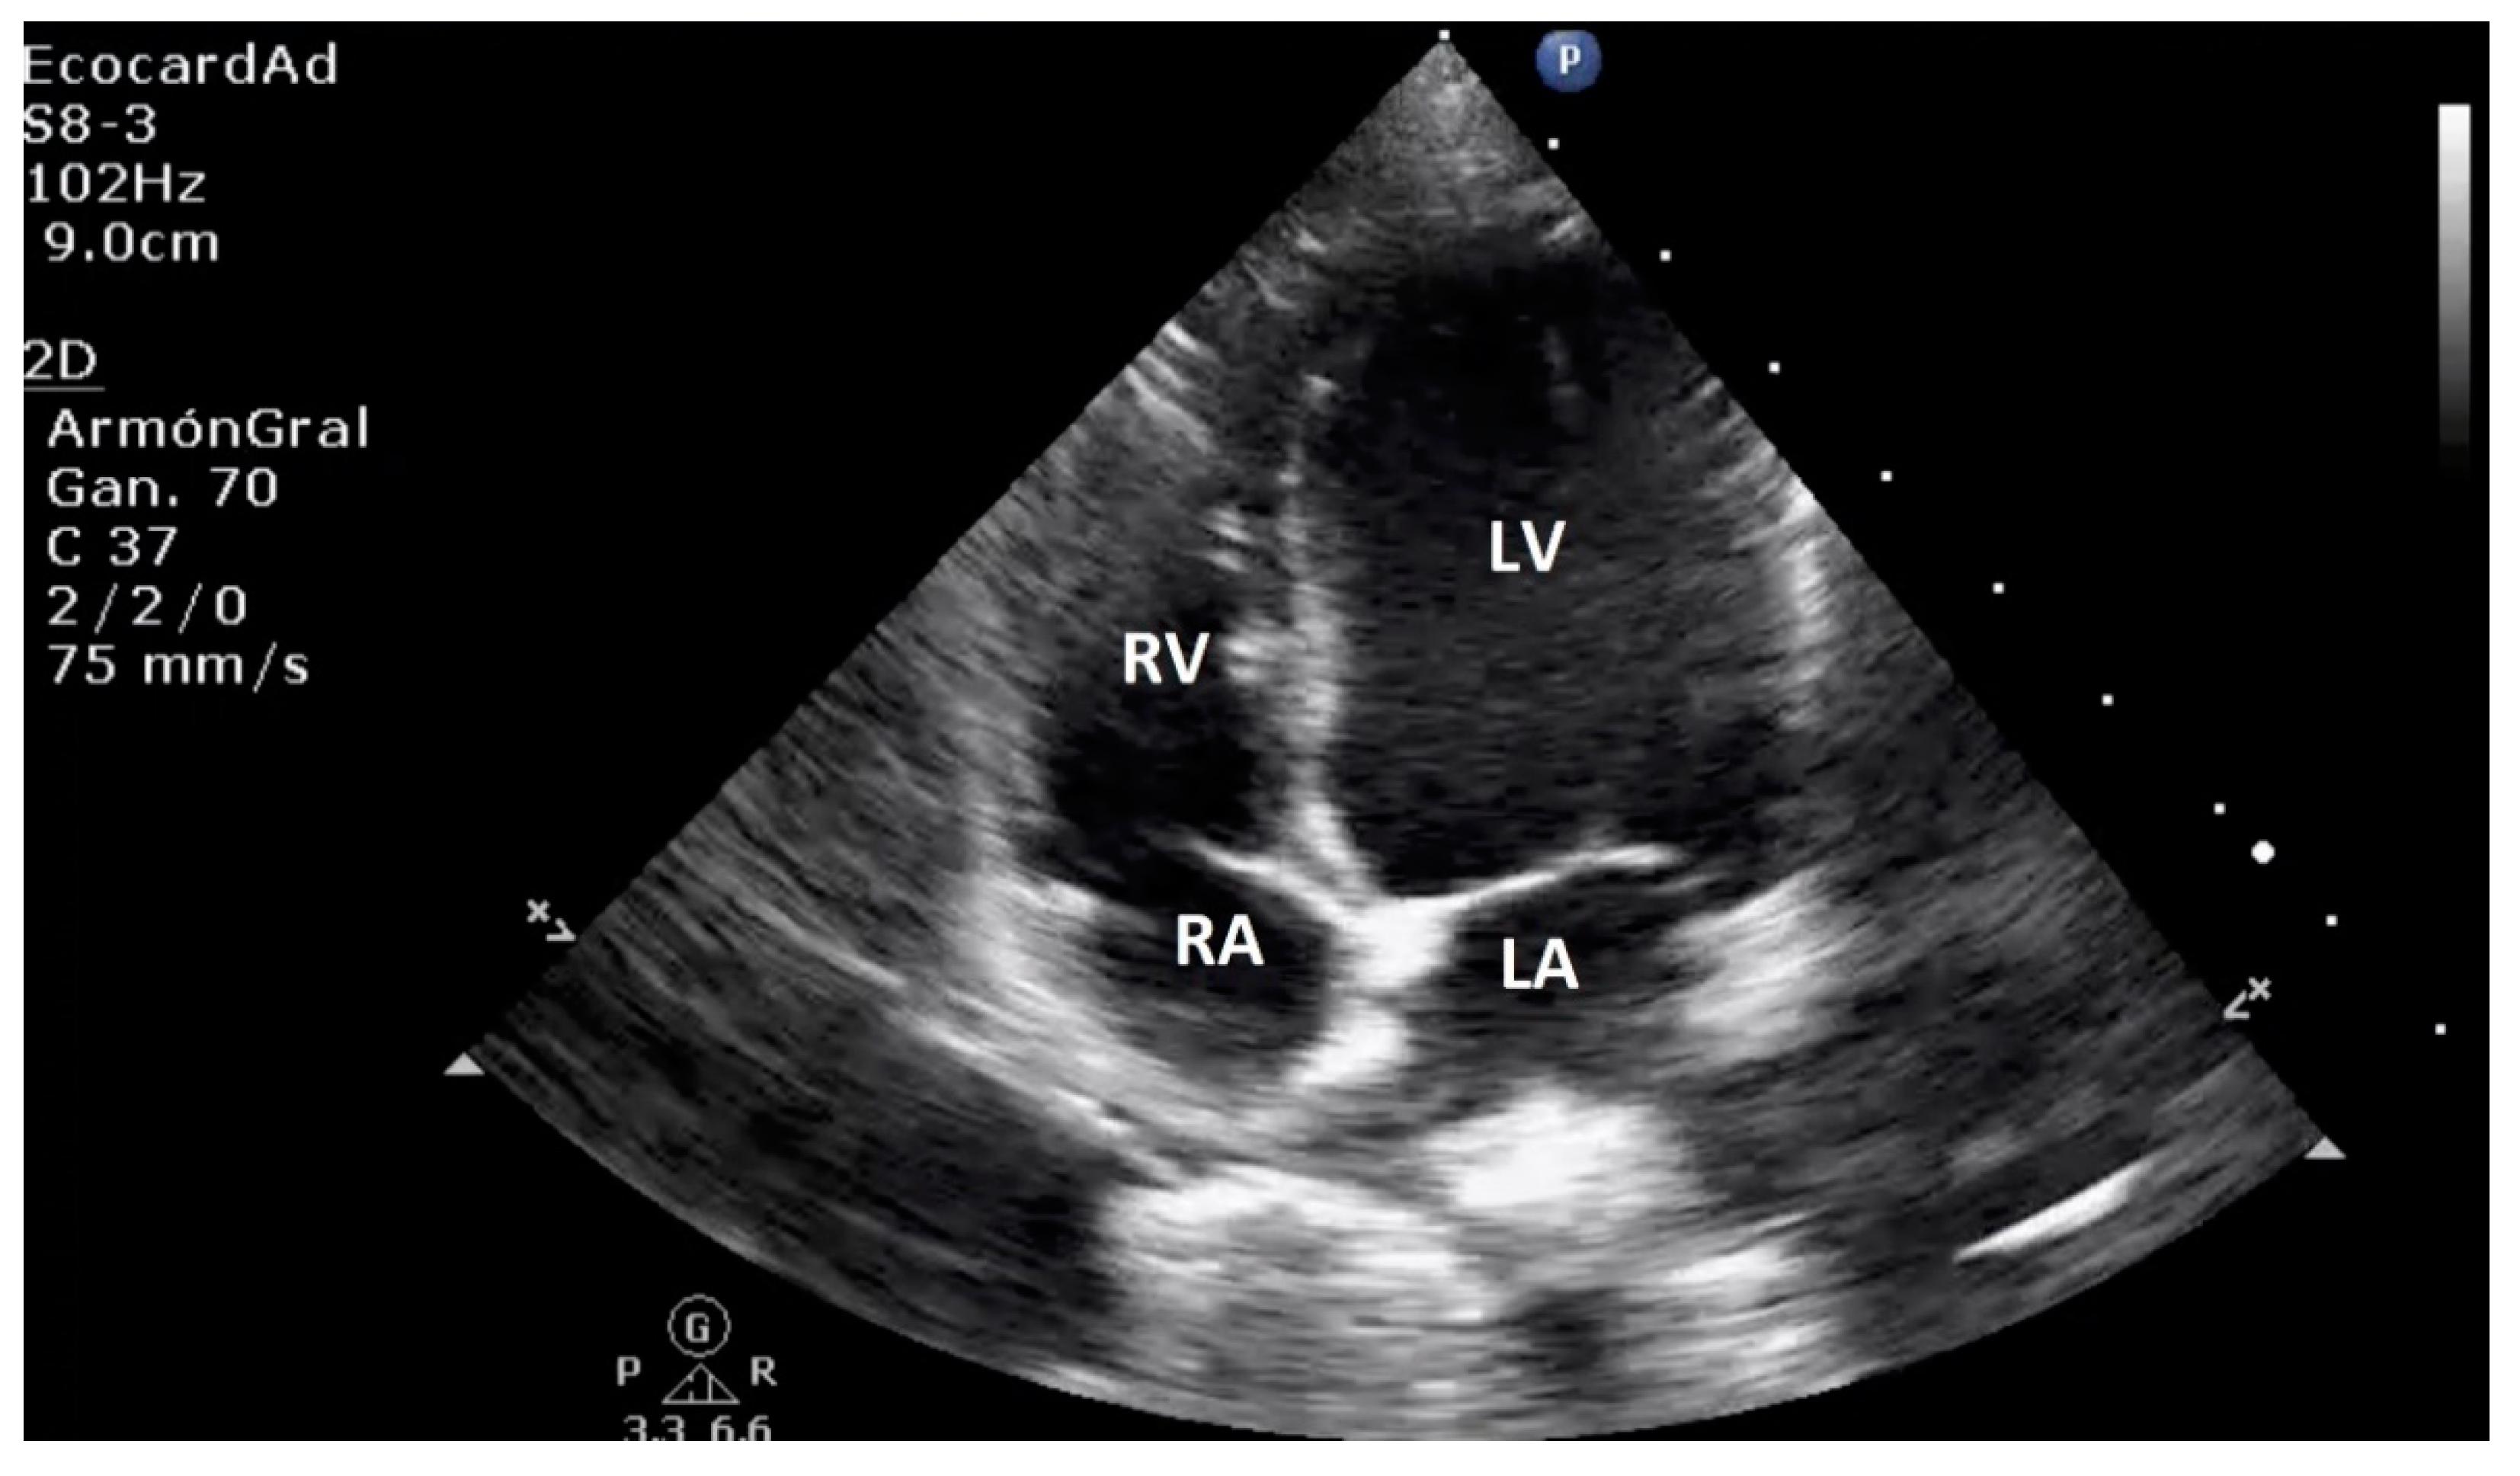

4.3. Canine Myxomatous Mitral Valve Disease. Comparative Transthoracic Echocardiography with Human Mitral Valve Prolapse

4.6. Left Heart Remodeling Assessment and LA Evaluation

4.7. Comparative Left Ventricle Assessment

4.8. Key Main Useful Echocardiographic Considerations for the Approach of Mitral Endocardiosis in Canine Patients

| Normal Basic Echocardiographic Views | Human: Parasternal long axis, parasternal short axis, apical four chamber, apical four-chamber view, subxiphoid (subcostal), suprasternal view, and IVC views. Canines: Four-chamber right-sided parasternal long-axis view, five-chamber right-sided parasternal long-axis view, right-sided short-axis view of the left ventricle at the level of the papillary muscles, right-sided short-axis view at the level of the left atrium and aorta. |